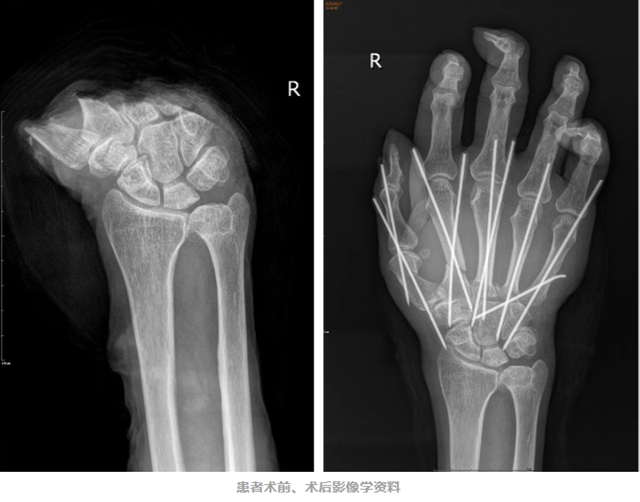

六月初,李某在干活时不慎被切割机割伤右手掌。瞬间,剧痛袭来,鲜血止不住地涌出,右手掌完全离断。

急诊科医生见状,不敢有丝毫耽搁,迅速为李某进行了简单的包扎止血处理。随后,李某以“右手掌创伤性切断”被收入骨伤科手外・儿骨・烧伤整形组住院治疗。

凭借丰富的临床经验和专业的医学知识,陈孝均带领团队很快确定了手术方案。在排除了相关手术禁忌后,一场与时间赛跑的“右手掌断肢再植术+游离前臂flow-through静脉皮瓣修复手背创面+石膏外固定术”在臂丛麻醉下正式开始。

经过一番艰苦奋战,手术顺利完成,当看到断掌的血液循环逐渐恢复时,所有人都松了一口气。